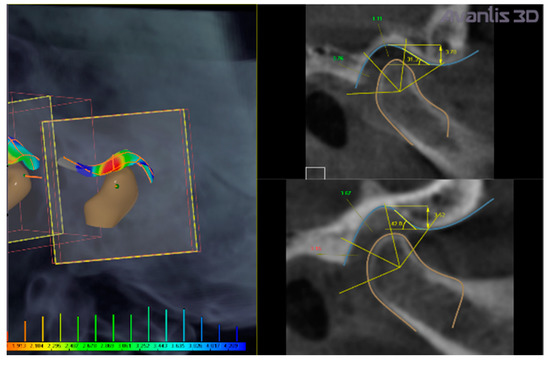

• Selection of condyles and TMJ fossa from CBCT data (Figure 3).

• Calculation of intra-articular spaces width (in mm) (anterior, superior, and posterior spaces) executed by the software (Figure 4).

In the present clinical case, CBCT images revealed a narrowing of the posterior intra-articular space width, in respect to normal values established by Rabukhina, that are: 1.7–2.7 mm for the anterior width; 3.1–3.9 mm for the superior height; and 3.4–4 mm for the posterior part) (Figure 3 and Figure 4) [21,22,23].

Figure 3. Calculation of intra-articular space widths on CBCT taken in habitual position. Colors evidence reduced (red), normal (green), and increased (blue) intra-articular space widths ranging from 1.9 to 4.2 mm.